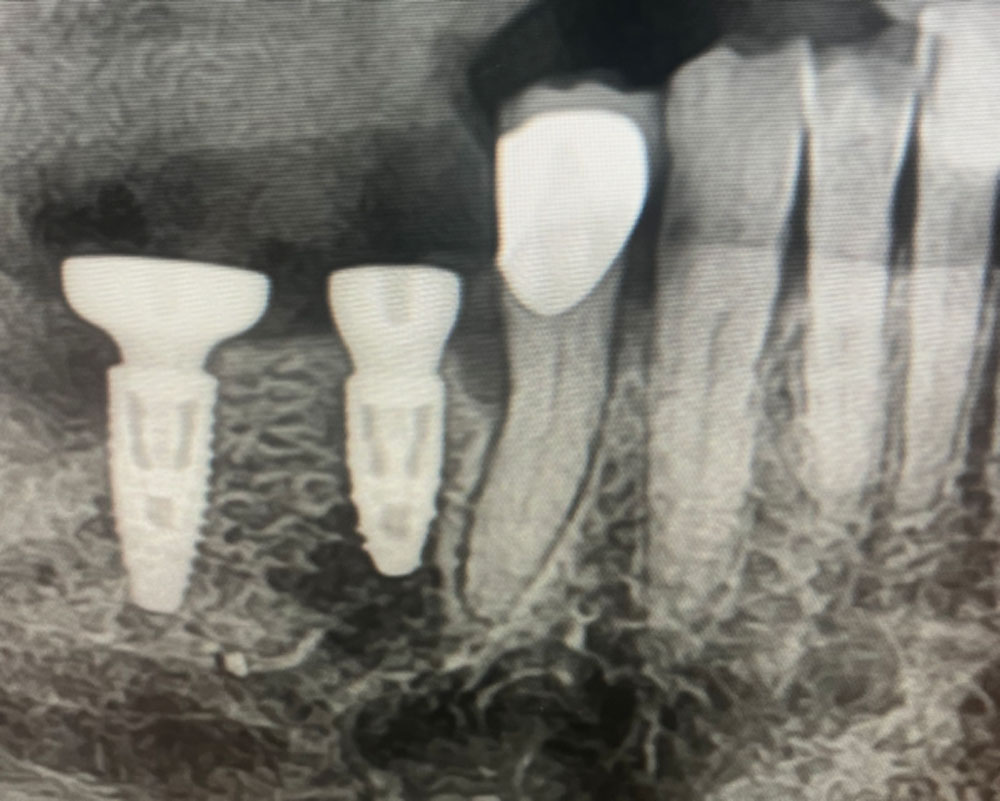

Un apport osseux a été effectué au niveau du site d’extraction, et une supplémentation en vitamine D a été prescrite afin d’optimiser la cinétique de cicatrisation.

Un second implant a été posé le même jour au niveau de l’élément intermédiaire du bridge. Un dent support du bridge ancien est conservée.

La cicatrisation est favorable et les implants s’intègrent dans un environnement osseux et gingival stable.